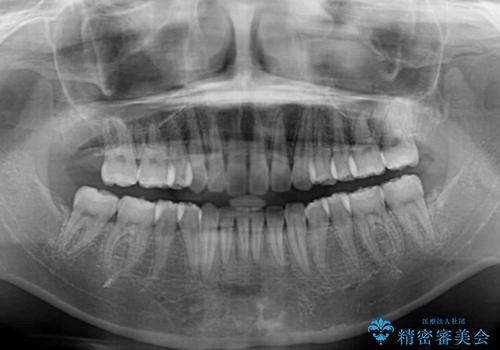

非抜歯矯正ではデコボコを解消することでより口元が突出する可能性があるため、上顎右右側の小臼歯1本の抜歯を行い、ワイヤー装置による矯正治療を行うこととしました。

正中位置を合わせるために、上顎臼歯部にアンカースクリューを埋入することとしました。

お仕事の予定を調整しやすく、平日の昼の時間帯に通院可能であったので、非常にスムーズに治療を進めることができ、1年半で無事に治療を終えることができました。